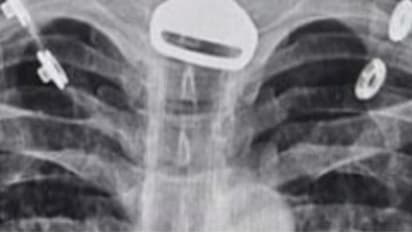

റിയാദ്: കടുത്ത ശ്വാസംമുട്ടലുമായി ആശുപത്രിയിലെത്തിയ 49 കാരനെ എക്സ് റേ പരിശോധനയ്ക്ക് വിധേയനാക്കിയപ്പോള് കണ്ടത് കാറിന്റെ താക്കോല്. ശ്വാസനാളത്തില് കുടുങ്ങിയ നിലയിലാണ് താക്കോല് കണ്ടത്. സൗദി അറബ്യേയിലാണ് സംഭവം ഉണ്ടായത്.

ശ്വാസമെടുക്കാന് പ്രയാസം നേരിട്ടതോടെയാണ് 49 കാരന് സൗദിയിലെ അല് ഖുന്ഫുധാ ഗവര്ണറേറ്റിലെ ആശുപത്രിയിലെത്തിയത്. തുടര്ന്ന് ഡോക്ടര്മാര് നടത്തിയ എക്സ് റേ പരിശോധനയിലാണ് ഞെട്ടിക്കുന്ന വിവരം അറിഞ്ഞത്. ഇദ്ദേഹത്തിന്റെ ശ്വാസനാളത്തില് കാറിന്റെ താക്കോല് കുടുങ്ങിയതായി കണ്ടെത്തുകയായിരുന്നു.

താക്കോല് വായിലിട്ട് വെറുതെ കളിച്ചുകൊണ്ടിരുന്നപ്പോള് അറിയാതെ വിഴുങ്ങിപ്പോയതാണെന്ന് 49കാരന് പിന്നീട് ഡോക്ടര്മാരോട് പറഞ്ഞു. ഹൃദ്രോഗി കൂടിയായത് കൊണ്ട് ഇദ്ദേഹത്തിന്റെ ശ്വാസനാളത്തില് നിന്നും താക്കോലെടുക്കുന്നത് സങ്കീര്ണമായി. പിന്നീട് എന്ഡോസ്കോപ്പി നടത്തി. ലാപ്രോസ്കോപ്പി വഴി താക്കോല് അപകടമൊന്നും കൂടാതെ പുറത്തെടുക്കുകയായിരുന്നു. വിജയകരമായി താക്കോല് പുറത്തെടുക്കാനായി. ആരോഗ്യനില സാധാരണനിലയിലാകുന്നത് വരെ ആശുപത്രിയില് നിരീക്ഷണത്തില് കഴിയുകയാണ് 49കാരന്.